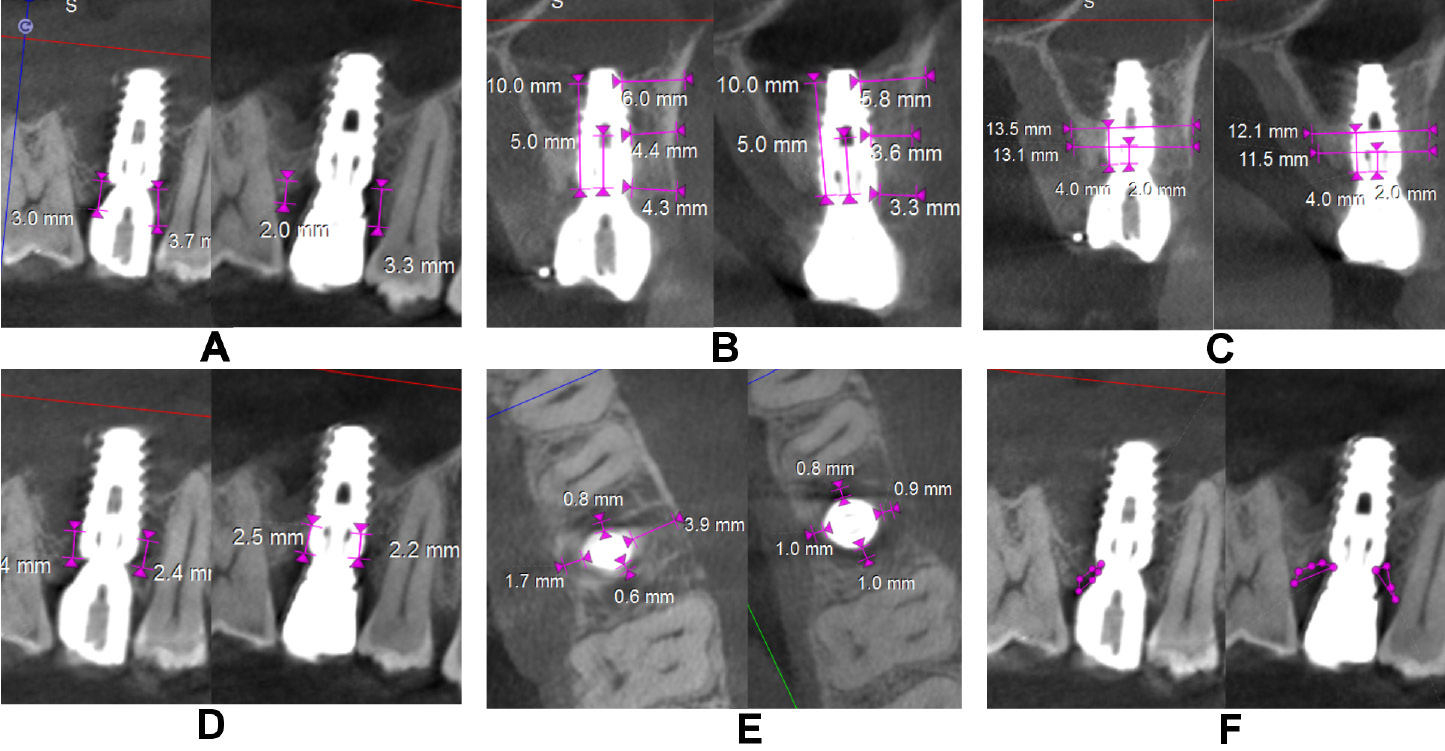

The clinical parameters assessed at baseline, and at 6 and 12 months were the modified plaque index (mPI),11 the modified sulcular bleeding index (mSBI),12 the probing depth/implant sulcus depth (PD),13 the gingival thickness (GT), and the Testori implant esthetic score (TS).14 Using CBCT, the following radiographic parameters were assessed on the day of surgery after implant placement and at 12 months (Figure 4 and Figure 5): the crestal bone height (CBH) – the distance between the implant shoulder to the most coronal point of the interproximal crestal bone height in the sagittal view15; the buccal bone thickness (BBT), measured at the crest, 5 mm from the crest and 10 mm from the crest in the coronal view16; the ridge width (RW) – the buccolingual dimension of the osseous ridge in the coronal view; the vertical distance (VD) – the distance between the first radiographic bone implant contact and the first implant thread on the mesial and distal sides, and the amount of bone loss on the mesial and distal sides in the sagittal view17; JS – the perpendicular distance from the most coronal point of the mesial, distal, buccal, and palatal bone crest to the implant platform in the axial view; and the radiolucent area (RA) – the area between the implant shoulder and the bone crest in the sagittal and coronal views.18 Discomfort/pain was assessed on the day of implant surgery, and patient satisfaction at 12 months postoperatively – both using the visual analog scale (VAS) (Figure 6).

In the control group, CBH-mesial (2.33 ±0.62 mm, 1.95 ±0.41 mm), CBH-midfacial (2.49 ±0.73 mm, 1.88 ±0.49 mm), CBH-distal (2.32 ±0.68 mm, 1.87 ±0.46 mm), BBT at the crest (1.46 ±0.53 mm, 1.18 ±0.41 mm), and RW at 4 mm from the crest (8.57 ±1.01 mm, 8.10 ±0.82 mm) showed a highly significant decrease from baseline to 12 months in contrast to the test group. Similarly, VD-mesial and VD-distal showed an increase in the mean value in the control group (p < 0.001). A highly significant decrease from baseline to 12 months in JS-mesial (1.23 ±0.44 mm to 0.36 ±0.32 mm, and 1.37 ±0.35 mm to 0.91 ±0.39 mm), JS-distal (1.45 ±0.55 mm to 0.29 ±0.41 mm, and 1.06 ±0.47 mm to 0.94 ±0.25 mm), JS-buccal (2.34 ±0.58 mm to 0.43 ±0.40 mm, and 2.20 ±0.30 mm to 1.45 ±0.38 mm), and JS-palatal (1.11 ±0.48 mm to 0.42 ±0.34 mm, and 1.20 ±0.63 to 0.82 ±0.42 mm) was noted in both the test and control groups, respectively, except for JS-distal in the control group. A significant increase (p < 0.05) in RA on all sides was observed in the control group and on the buccal side for the test group (Table 4).

The intergroup comparison for the mean change in the radiographic parameters after adjusting to the respective baseline values showed statistically significant differences in all radiographic parameters except for CBH-distal, BBT at 5 mm and 10 mm from the crest, VD-mesial, and RA-distal. Highly significant differences were observed with regard to the change in RW at 4 mm from the crest (9.80 ±0.89 mm), VD-distal (1.35 ±0.43 mm), JS-mesial (0.38 ±0.34 mm), JS-distal (0.25 ±0.34 mm), JS-buccal (0.42 ±0.39 mm), RA-mesial (0.63 ±0.48 mm2), and RA-buccal (0.19 ±0.47 mm2) in the test group as compared to the control group at 12 months (Table 5).